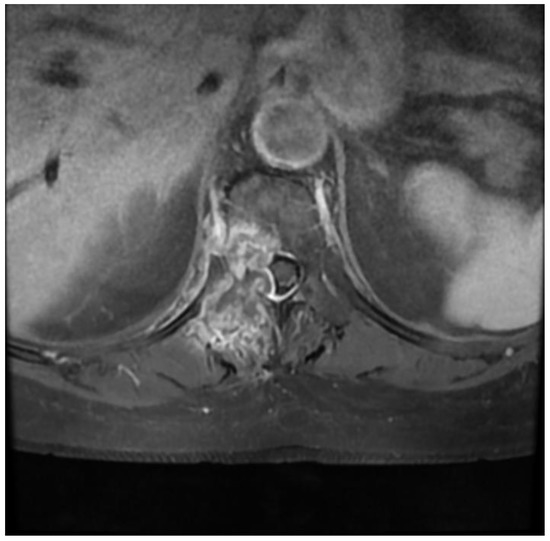

Fully Endoscopic Spine Separation Surgery in Metastatic Disease—Case Series, Technical Notes, and Preliminary Findings

2. Materials and Methods

3. Results